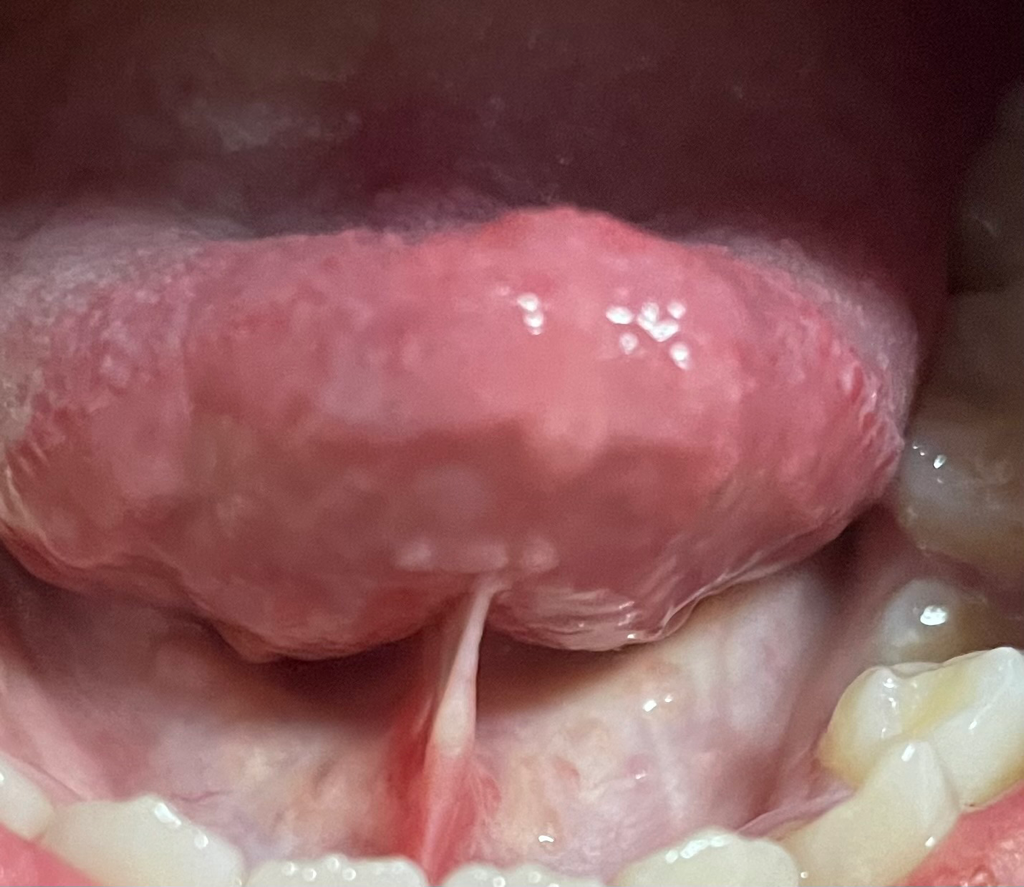

설소대가 붓고 그 주변이 다 하얘요.

안녕하세요... 아까 설소대가 아파서 거울을 봤는데 설소대가 부어있고 그 밑? 근처 부분이 다 하얗게 변했습니다... 왜 이런 건가요 ㅠㅠ 제가 지금 인후염? 감기?에 걸려서 컨디션이 좋지는 않아요.

설소대는 자극을 받으면 부을수 잇지만 옆부분은 설소대가 당겨지면서 하얗게 보여지는거 같습니다. 문제가 잇어 보이진 않습니다.

사진으로 봤을 때는 크게 문제가 보이진 않습니다 설소대 부위가 음식물에 의해서 자극이 되었다면 일시적으로 불편할 수 있으며 대부분 시간이 지나면서 괜찮아지는 경우가 많습니다.

치과에서 구강내과는 구강내 연조직의 이상을 확인하는 과이기 때문에 구강내과에서 진료를 받아 오는 것을 권해 드립니다.

몇가지 가능성이 있으나 현재로서는 컨디션 저하로 인한 일시적인 증상 또는 설하선염이 의심됩니다. 설하선염 같은 경우는 혀 밑에 있는 침샘의 염증이고 심해지면 통증, 오한, 발열 등이 동반됩니다. 아주 심한 경우가 아니라면 항생제와 진통제 약 처방 통해 증상을 완화시킬 수 있습니다. 치과를 내원해보시기 바랍니다.